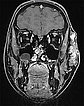

Coronal, T2-weighted fat-suppressed MRI of the face. The venous malformation typically appears very hyperintense (white).

Coronal, T1-weighted MRI of the face. The venous malformation appears isointense to the musculature and is embedded in the surrounding fatty tissue.

Coronal, T1-weighted fat-suppressed MRI of the face after administration of contrast medium. The venous malformation enriches the contrast medium more clearly after 4 minutes, but relatively slowly and not yet completely at the time of imaging.